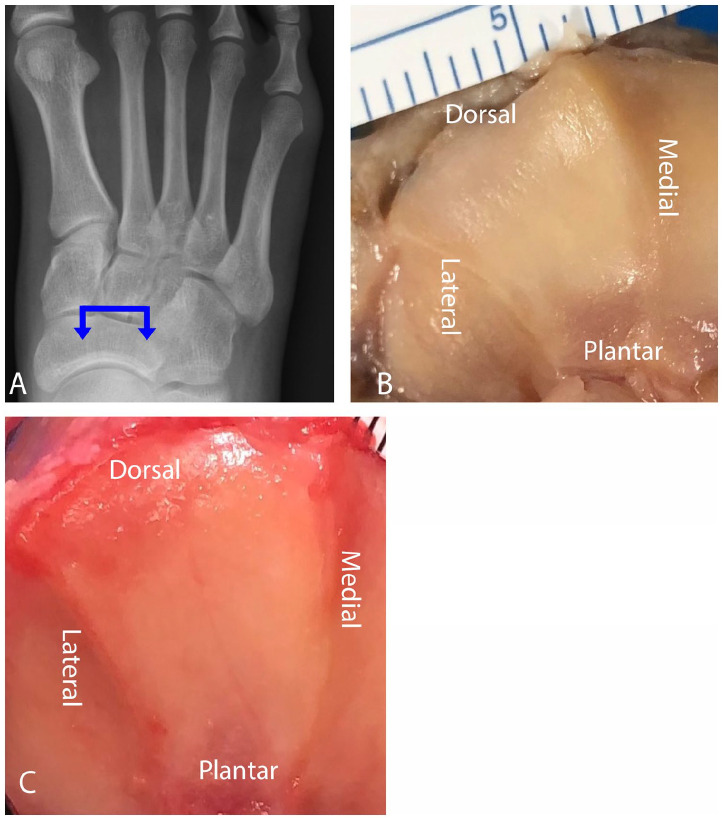

Figure 1.

(A) The proximal medial cuneiform articulation. The blue arrow denotes the direction of the viewing plane. (B) The “arrowhead” variant takes on the shape of a modified traditional triangle with a convex plantar base, 2 rounded corners at the base, and a dorsal directed apex. The majority of the fibrous component was located plantar. (C) The “rhomboidal” variant outlined by a rim of fibrous tissue dorsally, medially, and plantarly, with the fibrous thickening plantar to the articular cartilage.

For the proximal medial cuneiform articulation, the total mean surface area was 272 ± 61 mm2, with 69.6% of the area composed of articular cartilage (Table 1). The shape of the articular cartilage had 2 variations: arrowhead-shaped and rhomboidal (Figure 1). The arrowhead variant was the most common shape appreciated (70%, 14 of 20 specimens) and the rhomboidal variant was noted in 30% of specimens (6 of 20). The arrowhead variant had the basic shape of a traditional triangle; however, slightly modified with features of a convex plantar base with 2 rounded corners and a dorsal-directed apex. The fibrous aspect of the articulation could be found dorsal at the apex, as well as medial and plantar to the articular cartilage with most of the fibrous component located plantar. The rhomboidal variant was outlined by a rim of fibrous tissue dorsally, medially, and plantarly with the fibrous tissue thickening plantar to the articular cartilage. All surfaces of the articulations were found to be concave.